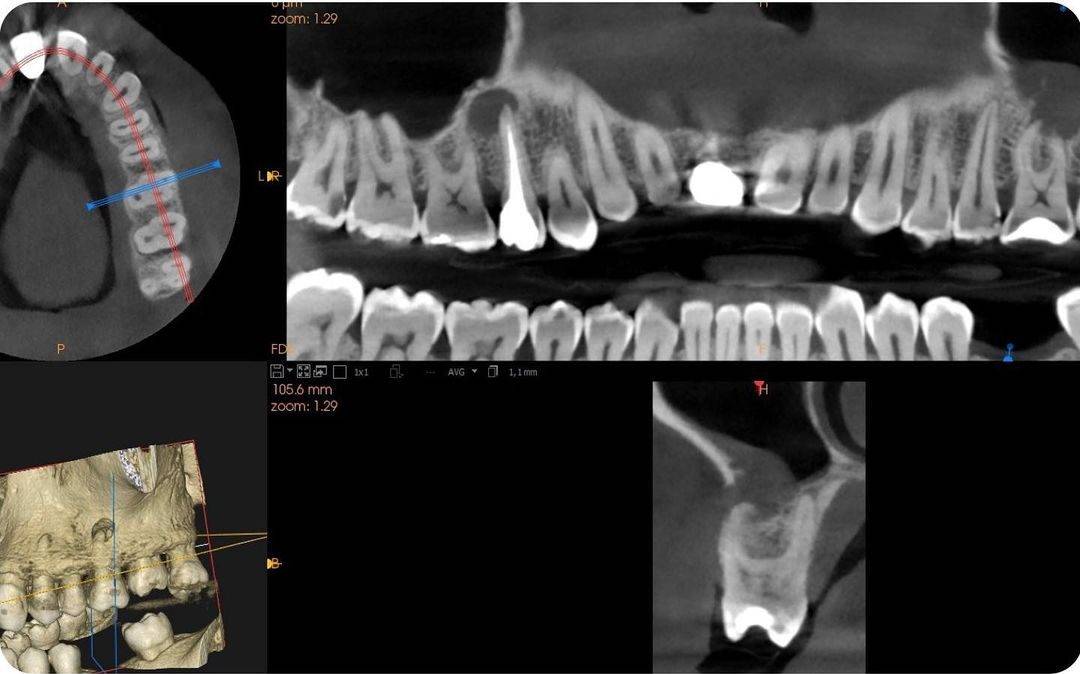

Tratadores de conducto endodoncia en 26 e implante dental en 15. Revisión a los 18 meses.